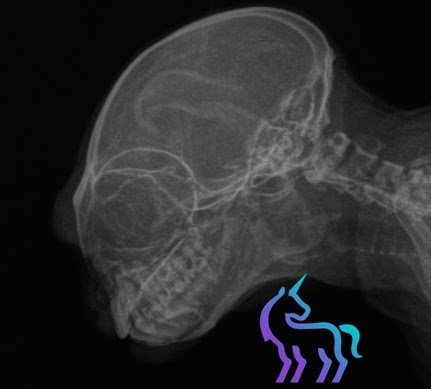

Radiographie tête de lémurien © Lingostière Clinique Vétérinaire dans l’Art Radiographique